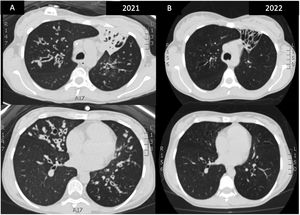

A 25-year-old woman diagnosed with cystic fibrosis (CF), homozygous F508del mutation, who started treatment with triple therapy with elexacaftor/tezacaftor and ivacaftor as compassionate use due to unfavorable evolution. Chest CT before the start and after 18 months of treatment (Fig. 1) reveals important radiological changes with a decrease in the size of bronchiectasis and resolution of severe bronchial thickening, mucoid impacts and areas of atelectasis and consolidation. the Bhalla score rose from 7 to 20. Lung function improved with an FEV1 value of 690ml (25%) prior to the start of treatment and a value of 2170ml (77%) after 18 months of treatment.

(A) HRCT prior to initiation of treatment: complete atelectasis of the LSI and lingula with beaded and cystic bronchiectasis with severe bronchial thickening. (B) Control HRCT after 18 months of treatment: resolution of mucosal impactions, bronchial thickening and resolution of complete atelectasis in LSI, with beaded bronchiectasis without being occupied by secretions.